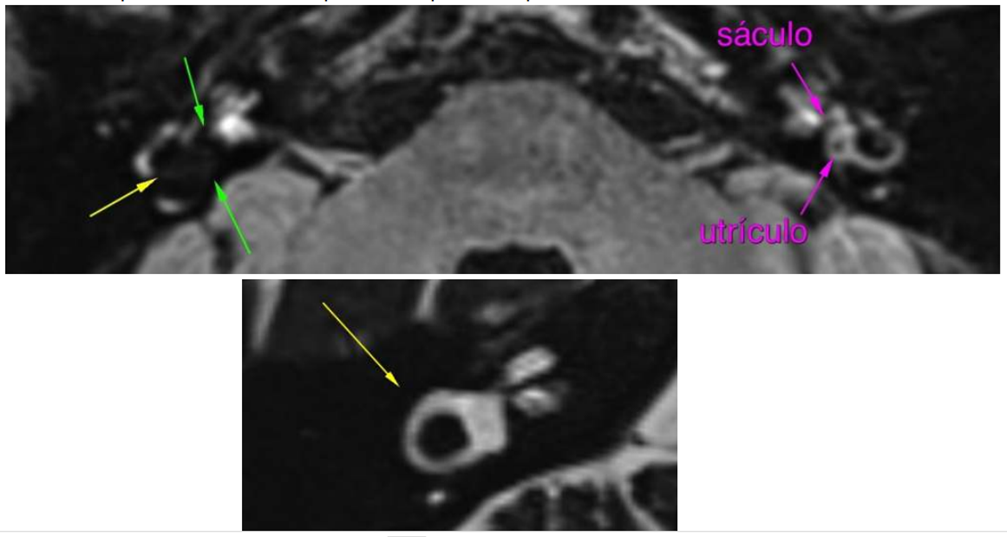

Não há sinais de hidropsia cocleovestibular à esquerda (setas roxas).

Há obliteração completa do vestíbulo à direita (hidropsia vestibular acentuada grau III – seta verde). Destaca-se, ainda, extensão da alteração do sinal relacionada à hidropsia ao canal semicircular lateral junto à confluência com o vestíbulo deste lado (seta amarela), sendo

que o mesmo, assim como todo o labirinto membranoso, tem sinal preservado na sequência fortemente ponderada em T2 o que indica que estão pérvios.

Observa-se, também, alargamento do espaço endolinfático coclear à direita, com obliteração parcial e irregular da scala vestibuli (hidropsia coclear grau I de Baráth – seta vermelha).

Comentário: Chama a atenção o grau acentuado de hidropsia endolinfática no lado direito que aparentemente se estende ao canal lateral do mesmo lado.

Schuknecht já descrevia em 1974 que em hidropsias severas poderia ocorrer herniação para o segmento não ampular do canal lateral